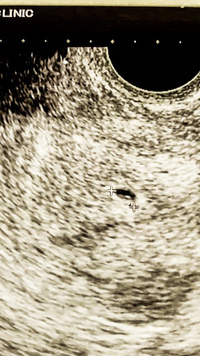

BT17 胎嚢小さい? 妊娠週数だと5週1日です。 胎嚢は4ミリ。 と言われたので悪い予感がして、待合室で胎嚢の大きさを検索。 小さい明らかに小さい。 「胎嚢確認出来ましたね。 では次の診察は一週間後の~」 とまたサッサと話が進んでいくので、慌てて「胎嚢小さくないですか? 」と質問し胎嚢確認bt17/klc16 40歳「ドリー」の女の子ママ ︎育児生活ブログBT17 とくに症状なしです BT16の5w0d 胎嚢が見なかったので 普通の胎嚢のサイズを探してみました! それっぽい研究資料ををみつけたのでそこから 胎嚢の大きさ 4w2d →15mm

胎嚢確認できて良かった という安心感はあったけれど、 なんとなく大きさが気になってネットで検索しちゃうとね、 女医先生は「順調」って言ってくれたけれど、 前も5W6Dで9.8mmの胎嚢が · BT17 胎嚢確認 5w1d まずは数値から↓ E2 2267 P4 06 βHCG この日、朝茶色い出血があり焦る。 茶色だけど出血は出血どきどきしながら病院へ行きました。 結果、HCGが驚きの伸びを見せてくれました! そして胎嚢も無事確認!サイズは58mmと小さめ。 ネットでいろいろ見てると大きさが心配になるものの、とりあえずホッとしました 出血については、茶色胎嚢は、62mmでした。 夢クリの基準値(BT17)が510mmとの事でしたので BT18の判定という事を考慮すると かなりギリギリの数値ではありますが (この時期胎嚢は1日1mm成長) 何とか基準値内はクリアしてくれました。 先生からは

· 今日、BT17の5W1Dで胎嚢確認に行って参りました。 16:12 受付 16:44 内診 17: 診察 17:25 会計 無事に、胎嚢確認できました〜! 大きさは10.6ミリ 内診室で「胎嚢ありますね。 · 先日 BT17 の通院でした。 本来なら胎嚢確認の診察日です。 私はhcgが上がらず、すでにBT12で下がり始めて、生理も始まっていたので(この日でday4)、この日はhcgがどこまで下がっているかの確認日でした。 ちなみに、胎嚢確認のための通院なら、時間指定があります(ホルモン補充の人は8時